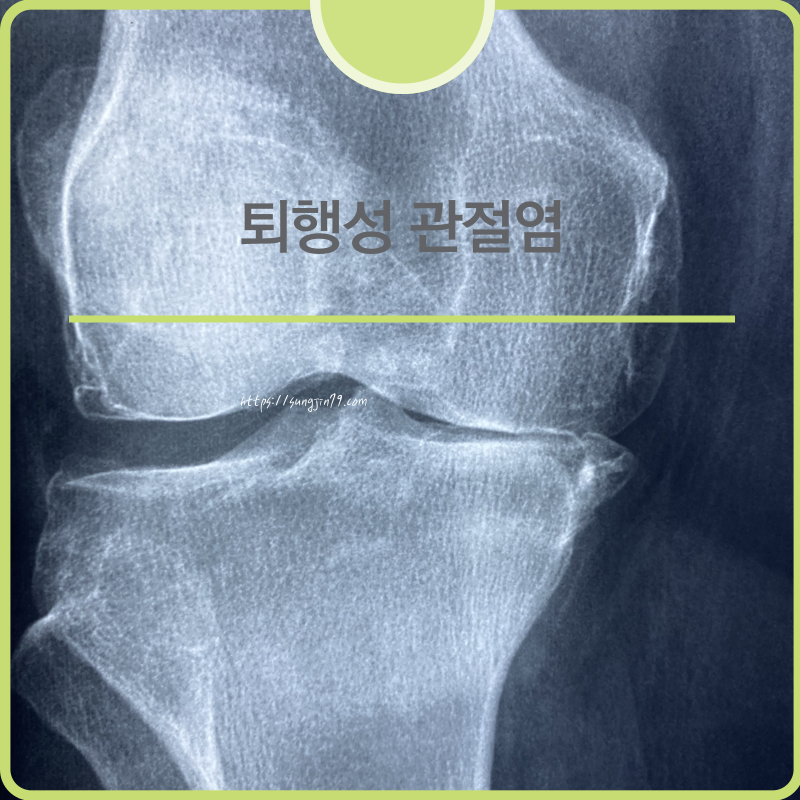

관절 통증, 그냥 방치하지 마세요!퇴행성 관절염(골관절염)이란?퇴행성 관절염은 관절을 감싸고 있는 연골이 점차 마모되면서, 연골 밑의 뼈가 노출되고 관절 주변에 염증이 생기는 질환입니다.